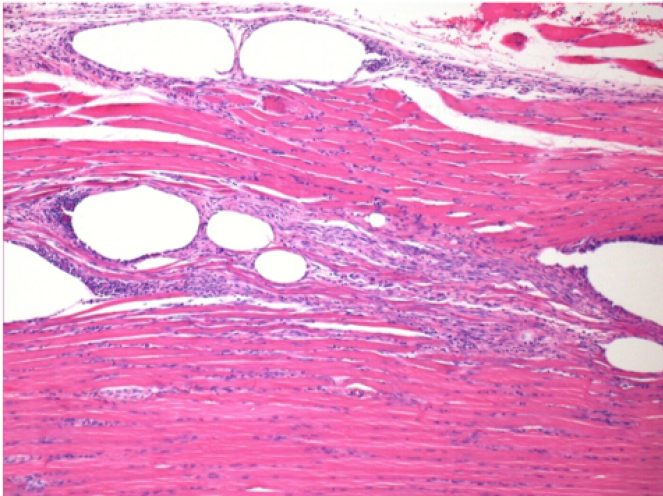

بعد 3 أشهر من حقن إندوبيل

3 أشهر (D90) بعد حقن Endopeel 0.1 مل في العضلة أمام الظنبوب اليمنى.

L : Control-100xD90

R:100xD90